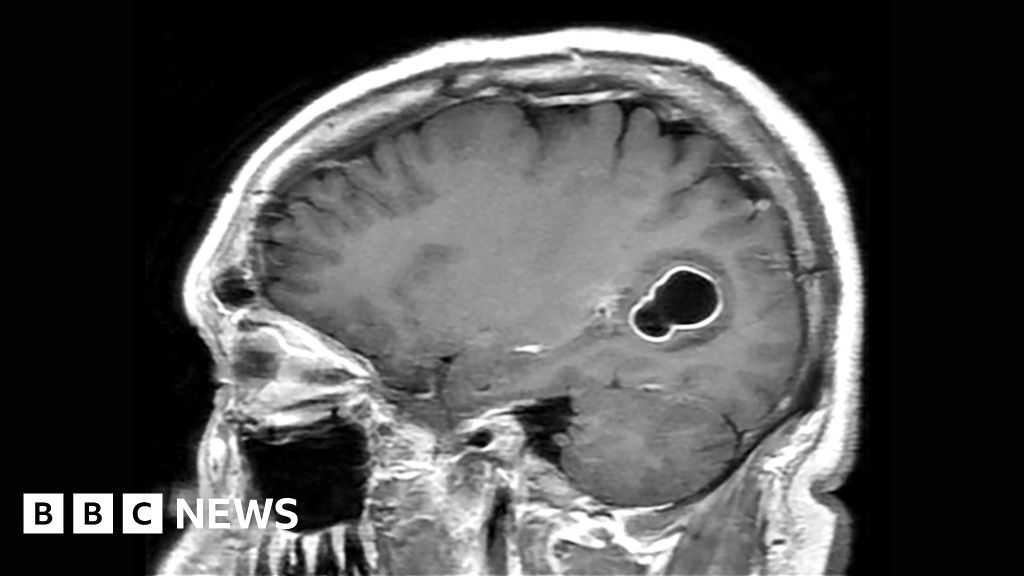

Doctors say a 52-year-old US man infected himself after contracting a tapeworm from undercooked pork.